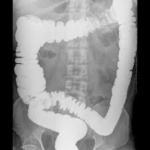

Los tipos especiales de exámenes de rayos X llamados estudios de contraste utilizan tintes con base de yodo o materiales de contraste, como el bario, junto con las radiografías para que los órganos aparezcan en la radiografía y obtener mejores imágenes. Por ejemplo, las radiografías del tracto gastrointestinal inferior, normalmente llamado examen de enema de bario, se emplean para tomar imágenes después de que el intestino se llena con sulfato de bario. Otro estudio, un pielograma intravenoso, usa un colorante especial para examinar la estructura y el funcionamiento del sistema urinario (uréteres, vejiga y riñones).

Radiografías del tracto gastrointestinal inferior (enema de bario): se puede restringir su alimentación durante algunos días antes del estudio. Se usan laxantes, enemas, o ambos, para vaciar el intestino grueso. Para el estudio, usted se acuesta y será sujetado a una mesa. Se toma una serie de radiografías. Luego el líquido de bario se coloca dentro del intestino por medio de un tubo pequeño y blando ubicado en el recto. El líquido se siente frío. Se procede a tomar más imágenes mientras la mesa le inclina a usted en diferentes posiciones. Esto ayuda a que el bario se mueva por los intestinos de modo que puedan verse en las radiografías. Tiene que permanecer acostado inmóvil y contener la respiración cuando se toma cada imagen.

Para obtener imágenes más claras, por lo general se realiza un examen con “contraste doble”. En este examen se usa una cantidad más pequeña de líquido de bario más espeso. Después que el bario está adentro, se hace ingresar aire en sus intestinos. Esto puede causar una sensación de hinchazón y malestar, junto con la ganas de vaciar los intestinos.